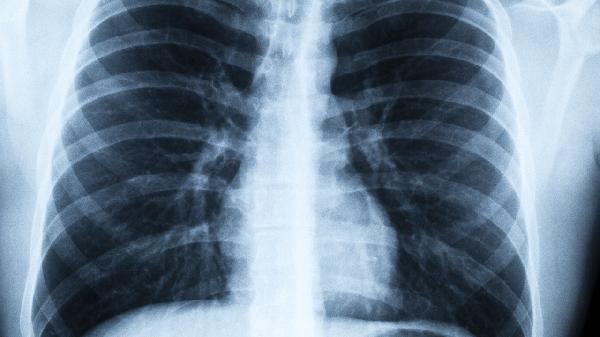

肺癌去世的人逐渐增多!提醒:一定不要做这几件事,保护肺部健康

肺部健康就像空气一样,平时感觉不到它的存在,可一旦出问题就是麻烦。最近不少人在讨论肺癌发病率上升的现象,其实很多风险因素就藏在我们习以为常的生活习惯里。